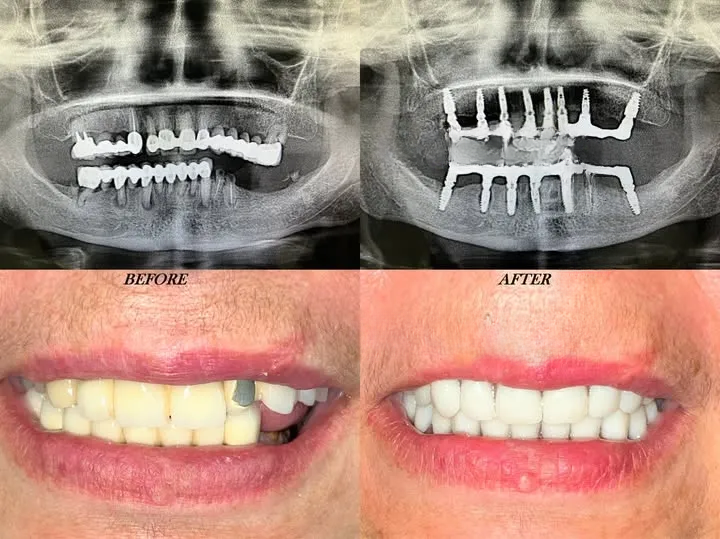

Réhabilitation globale

Réhabilitations Globales

Pour les patients nécessitant une transformation complète du sourire et de la fonction. Un nouveau départ avec un sourire parfaitement harmonieux.

Transformation totale Harmonie parfaite Nouveau sourire